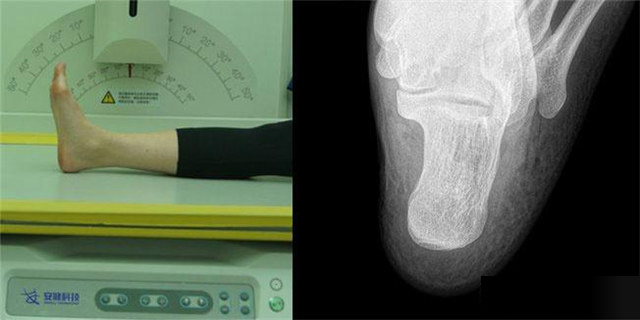

下肢:脛腓骨、踝、足脛腓骨長骨檢查需要包括--側的關節(jié)踝關節(jié)常規(guī)正+外側位,特殊時可選內斜位足常規(guī)前后正位+內斜位,外傷鑒定等情況,需要負重的水平側位(包括足尖和足跟)跟骨側位+軸位